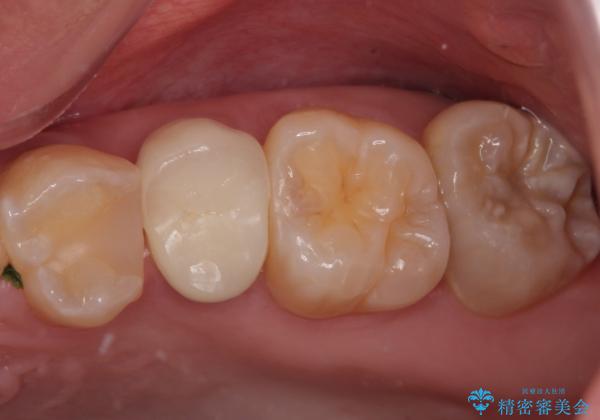

適合もよく、機能的に問題もなく、見た目も満足されていました。